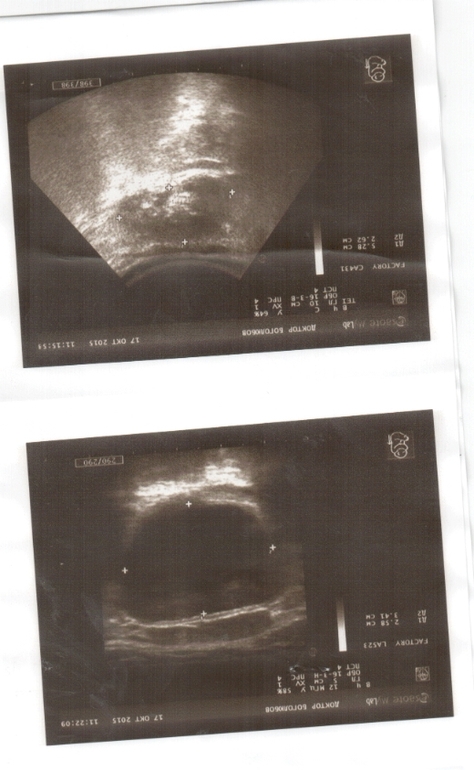

В поликлинике нам сказали, что с такими анализами нужна срочная госпитализация. Пошли мы делать узи. Узист только со второго раза смогла поставить диагноз. Говорила, что картина противоречивая.

Прилагаю все анализы и узи.

Скажите, правильно ли мы действуем? Или нам нужно срочно в стационар, как говорит педиатор? И вот эта дилатация чашечек до 9 мм. Очень меня беспокоит. Что скажете по этому поводу?